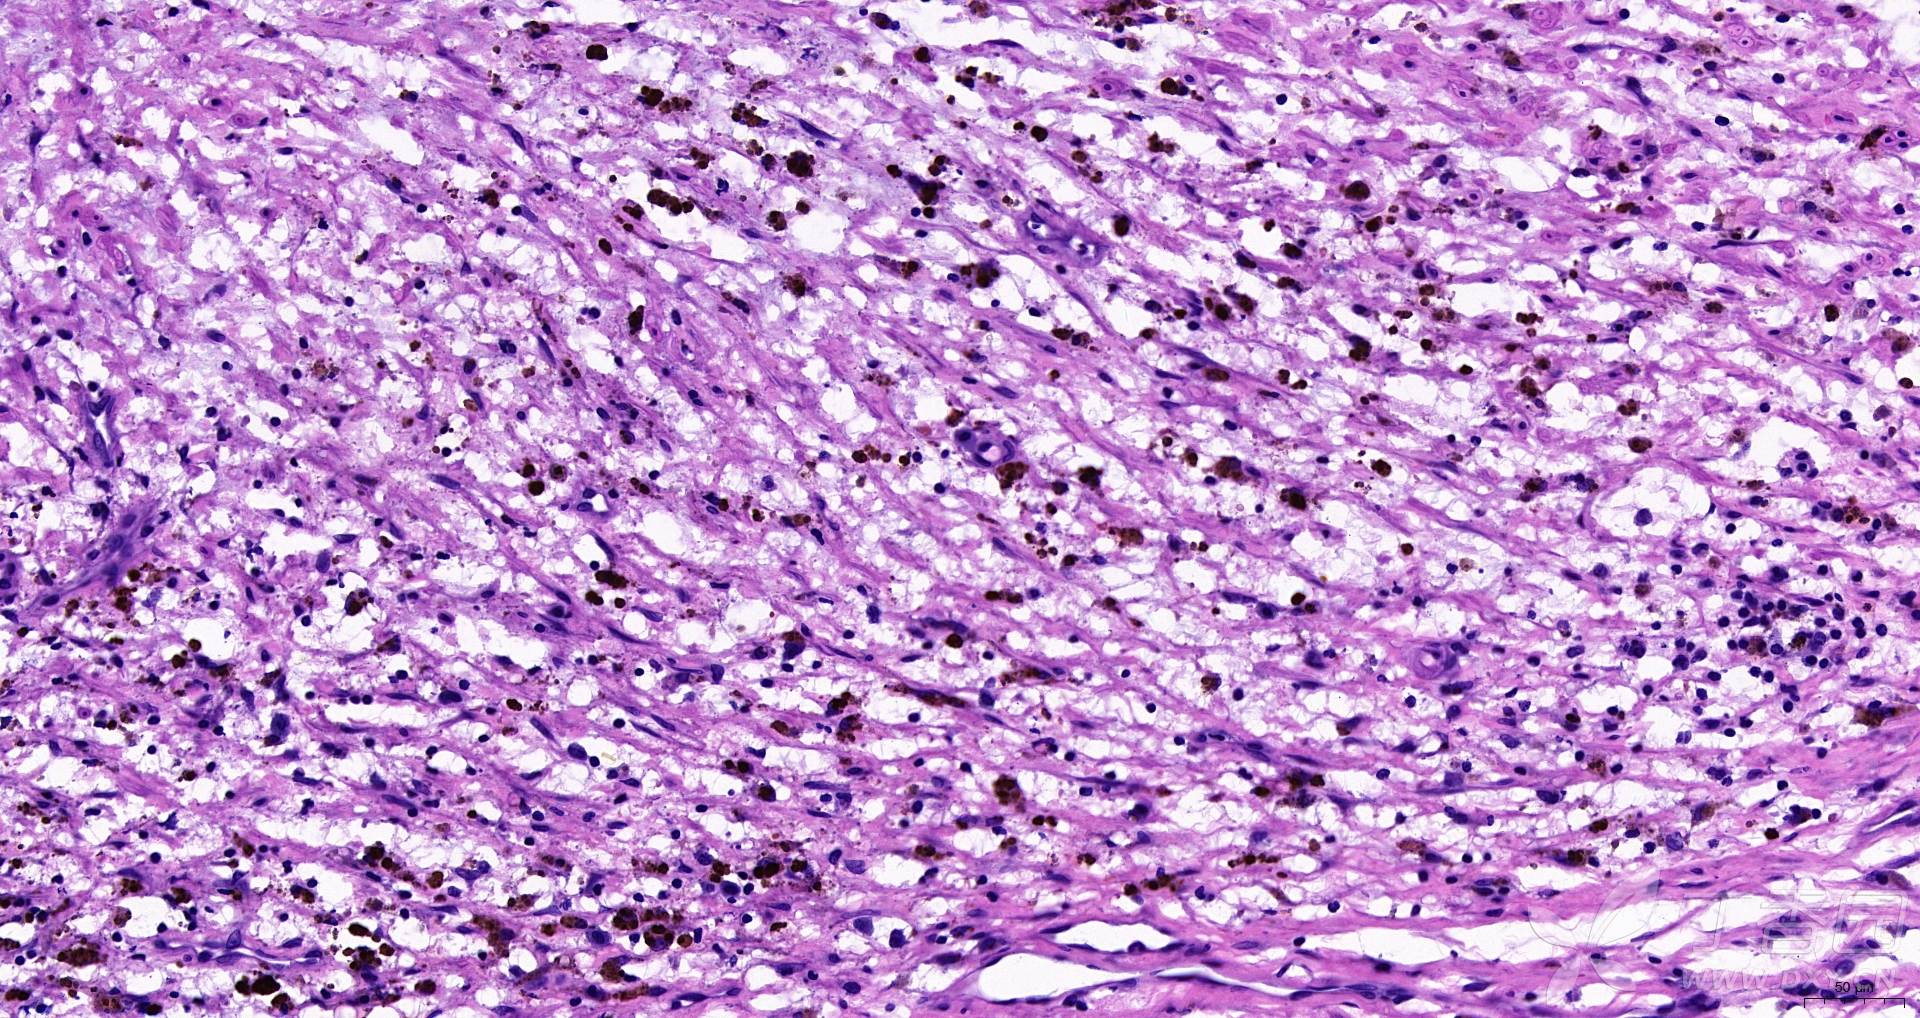

求助:人主动脉he染色切片 谢谢!

图片尺寸1920x1018